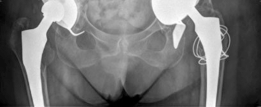

Initial radiographic assessment commenced with a comprehensive series of standard hip and pelvis views:

* Anteroposterior (AP) pelvis: Demonstrated significant superior and medial migration of the left acetabular component with evident periacetabular osteolysis. Lucency lines exceeding 2mm were observed at multiple interfaces, particularly zones 1 and 3 of DeLee and Charnley. There was evidence of prior bulk allograft incorporation, but with signs of partial resorption and failure to fully integrate into the host bone in areas of stress shielding. The femoral component appeared well-fixed in comparison.

* Lateral hip (true lateral or cross-table lateral): Provided further insight into the anteroposterior extent of component migration and bone loss. The superior migration was particularly pronounced, leading to significant disruption of the acetabular tear drop and potential intrapelvic protrusion if not contained.

* Judet views (Obturator oblique and Iliac oblique): These specialized views were crucial for detailed assessment of the anterior and posterior columns and walls of the acetabulum. The obturator oblique view highlighted significant superior and posterior column erosion, while the iliac oblique view showed extensive destruction of the superior acetabular dome and a large contained defect superiorly, consistent with substantial Paprosky type IIIb bone loss, potentially extending to type IV.